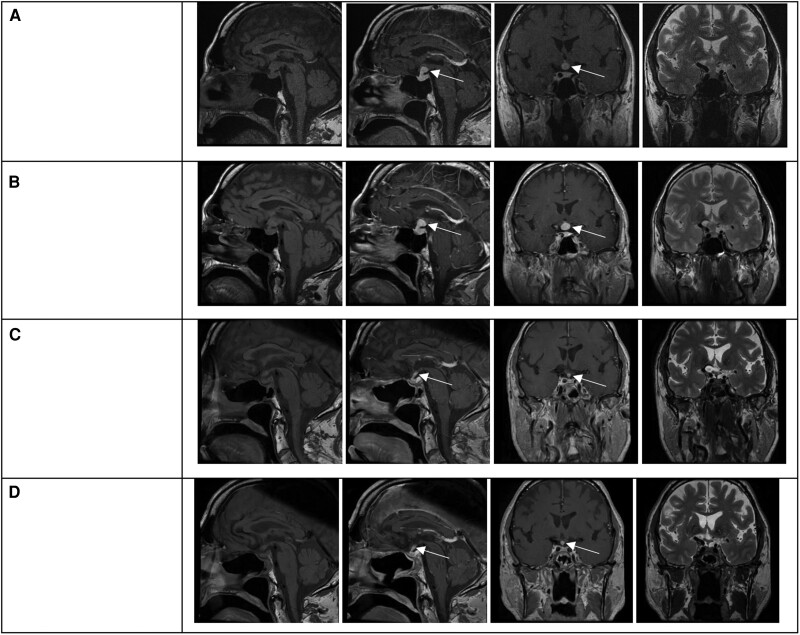

A 72-year-old man presented with several months of weakness, poor appetite, and depressed moods. Laboratory tests indicated central hypocortisolism, hypothyroidism and hypogonadism, and mild hyperprolactinemia. Imaging indicated a homogenously enhancing solid suprasellar mass inseparable from the hypothalamus and contiguous with a thickened proximal infundibulum. Neuro-ophthalmological evaluation was normal. Symptoms improved with hydrocortisone, levothyroxine, and testosterone replacement. After 6 months, transsphenoidal biopsy was performed due to mass enlargement and revealed fibrosis, lymphoplasmacytic infiltration, and CD138 and IgG4 staining. The levels of serum IgG4, complement, inflammatory markers, protein electrophoresis, amylase, and lipase and imaging of the chest, abdomen, and thyroid were unremarkable. After 1 month of prednisone therapy (starting dose 40 mg/day), the mass significantly involuted and remained stable afterward. Prednisone was gradually tapered to 5 mg daily over 10 weeks. During 22 months of follow-up, no systemic IgG4 disease was detected. Glucocorticoid, thyroid, and testosterone replacement was continued. This case of isolated IgG4-related hypophysitis illustrates the variable presentation that may not entail vasopressin deficiency or clinical mass effect. This entity should be considered in the differential diagnosis of suprasellar masses even in the absence of IgG4 systemic disease or characteristic serology. Management entails multidisciplinary collaboration and long-term follow-up.